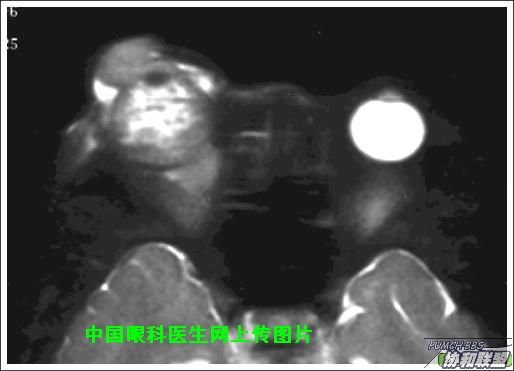

出院后半年发现右眼出现肿物,增长较快,随来京再次就诊(图1),转来我科。门诊检查发现:右眼无光感,结膜下肿物,突出睑裂。眼球突出,上移位。眶外侧可触及硬性肿物。超声(图2),CT(图3),MRI(图456)显示如图.